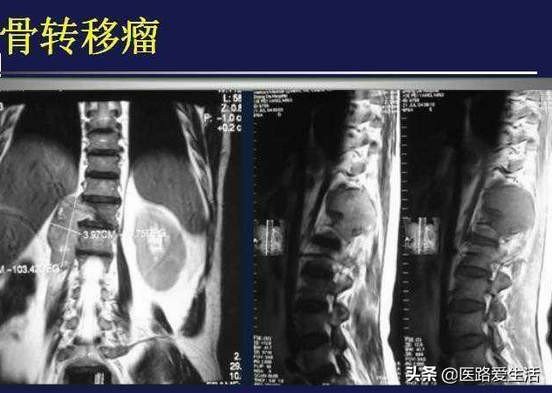

3.导致功能障碍、压迫症状 如:有些患脊髓肿瘤的人无论是良性、恶性也好,都有可能压迫神经引起瘫痪,关节周围的肿瘤因肿胀、疼痛往往会使关节不适或功能减退等。

2.还有CT可提示病变的横断面影像。

3.病理检查 可以切取或切除,另外也可以穿刺活检、简单、安全、损伤小、多用于脊柱及四肢。